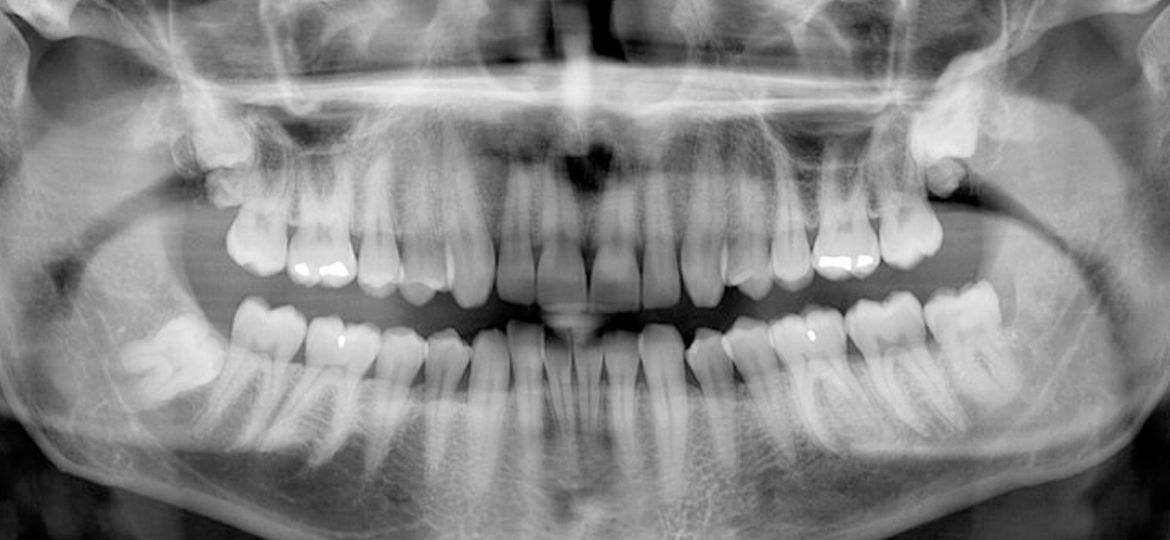

In simple terms, think of a Panorex X-ray as a grand, superhero image capturing your entire oral landscape in a single shot. It’s like stepping back and getting a holistic view of your teeth, jawbones, joints, and even your sinuses. Instead of the usual close-up shots, this panoramic perspective offers a comprehensive understanding of your oral health. And yes, you guessed it – Team Dental is all set to provide this game-changing service at one of their branches in your area.

Now, let’s explore why Panorex X-rays are not just about wisdom teeth but are also superheroes for your overall oral health. This panoramic image goes beyond the surface, revealing a range of dental issues, from hidden cavities to potential cysts. It’s the full picture your dentist needs to ensure your oral health is in top-notch condition.

A: A Panorex X-ray, also known as an OPG, is like a “superhero image” that captures a wide, single view of your entire mouth, including your teeth, jawbones, joints, and sinuses. Unlike traditional X-rays that provide close-up shots, the Panorex offers a comprehensive, holistic understanding of your oral health in one go.

A: Panorex X-rays are crucial for wisdom teeth as they precisely locate these teeth and help dentists assess if they are causing issues, aiding in decisions about extractions. Beyond wisdom teeth, they reveal a range of hidden dental problems like cavities or cysts, providing dentists with a full picture to plan effective treatments and preventive care for your overall oral health.